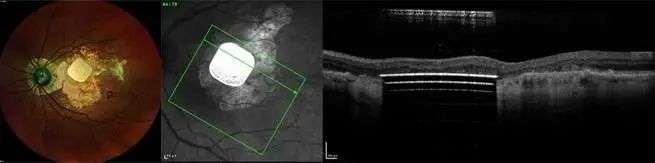

早在 2018 年,它们的小型无线光伏视网膜下植入物 PRIMA 就被 FDA 批准开始临床研究。

这是一种由无线视网膜下植入物和增强现实眼镜组合而成的「仿生眼」。

而且,它比 Argus II 更小、更简单、更便宜,还无需动脑部手术。

2019 年,法国 5 名患有晚期干性 AMD 的患者植入 PRIMA 的 12 个月数据表明,所有人的视网膜中央都成功引发了光感。

12 个月后,大多数患者可以识别字母,还有一定的字母序列,且没有与设备相关的不良反应,现在,他们正在欧洲和美国进行可行性试验。

PRIMA 为那些失去视力的老年人们,创造了一个仿生视觉的世界。